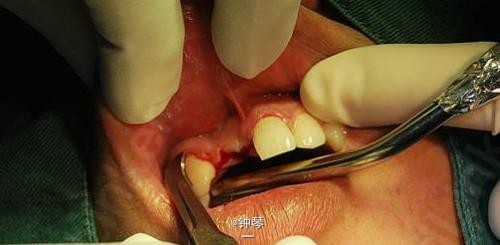

前牙种植+钛网应用

患者,女,30岁,右上1,2缺失要求种植。平素体质一般,否认高血压、糖尿病及心脏病史,否认肝炎、结核病史,无药物、食物过敏史,无外伤、手术及输血史。